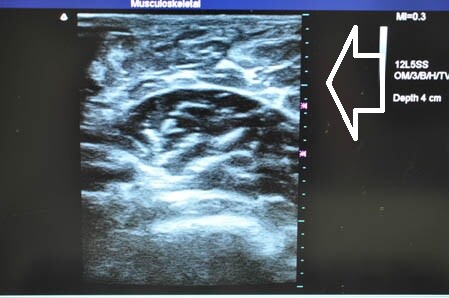

ではいつものように3Dタッチビュー(=超音波)で

皮下脂肪層を確認しながら見ていきましょう。

左ちからこぶ。

↓ ↓ ↓